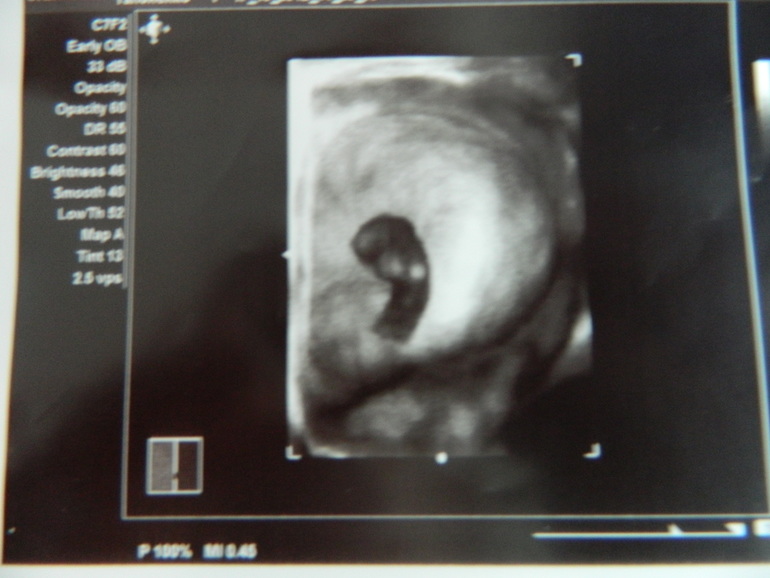

А вот это 3д и 2 д фотки моей крошечки в 10 недель беременности (по-моему самое трогательно, когда там еще вообще бусинка)